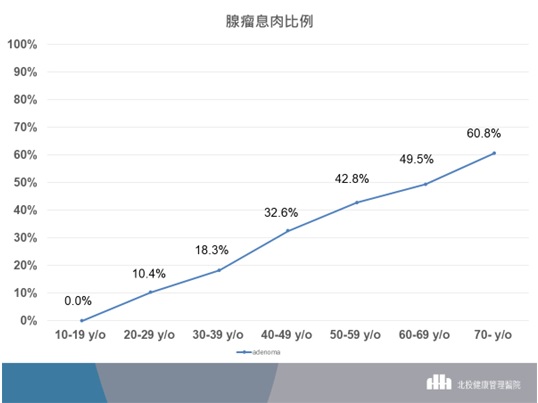

依照北投健康管理醫院內視鏡中心資料更進一步看看與未來大腸直腸癌有關的腺瘤息肉的比例,整體有腺瘤息肉的比例為36.2%(圖二),30-39歲的族群有腺瘤息肉的比例為18.3%,而40-49歲的族群有腺瘤息肉的比例也有32.6%。當然,與大腸直腸癌更相關的進展型腺瘤息肉,30-39歲的族群的比例為4.62%,而40-49歲的族群的比例也有6.39%(圖三)。

▲(圖二)以歷年統計資料來看,30-39歲的族群有腺瘤息肉的比例為18.3%,而40-49歲的族群有腺瘤息肉的比例也有32.6%。